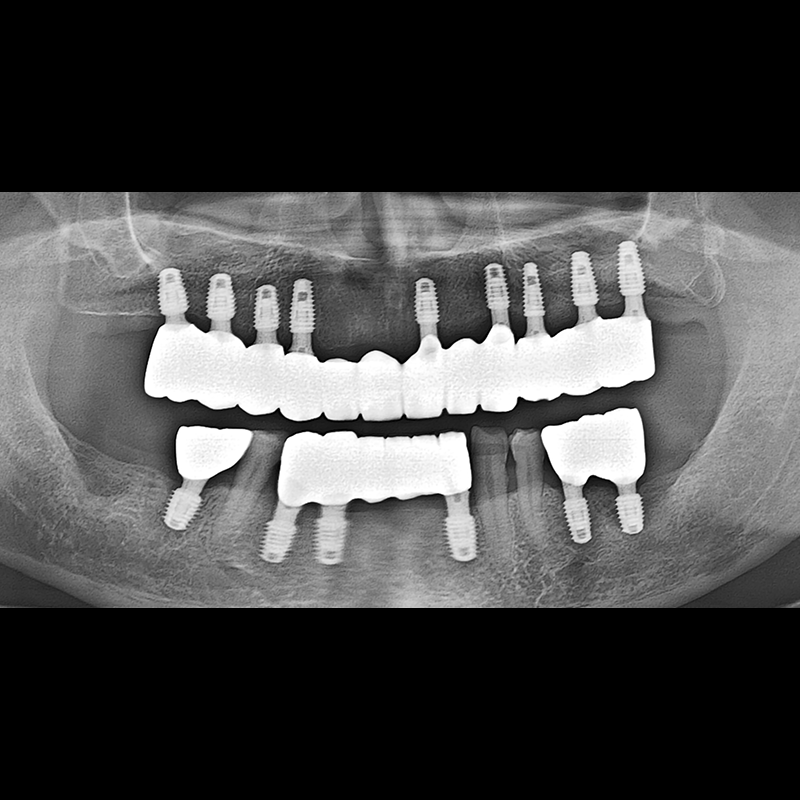

BEFORE AFTER

种植牙前后的照片 2025.05.30

在缺失的牙齿部分和难以挽救的牙齿位置植入了种植牙。